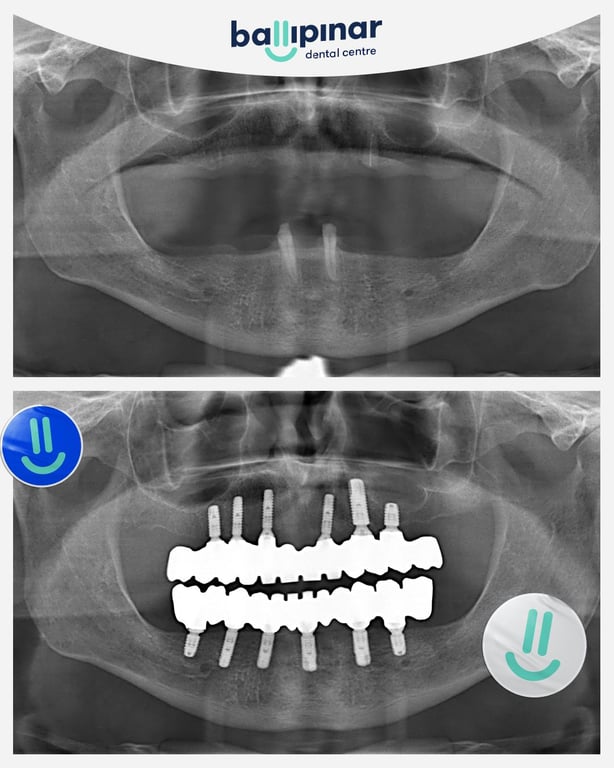

Dental implants Before & After

Explore all the before and after photos of dental implant procedures performed by Ballipinar in Turkey. Contact us today to achieve a beautiful smile.